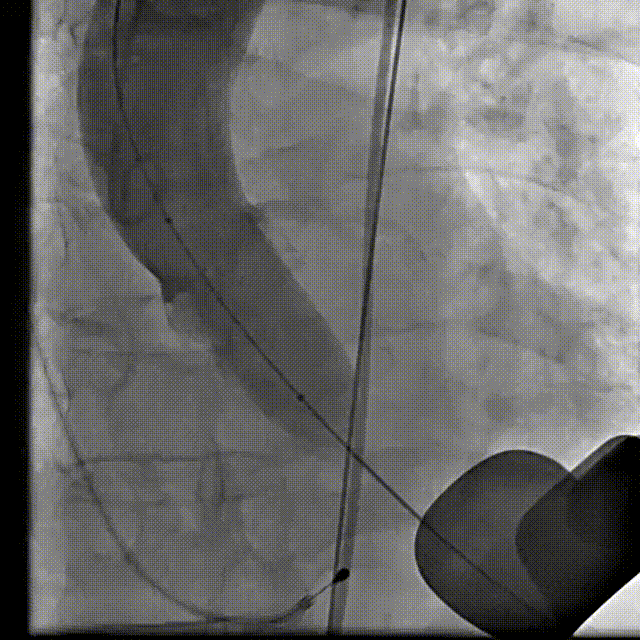

主动脉根部造影

18 mm球囊预扩张

输送系统到位